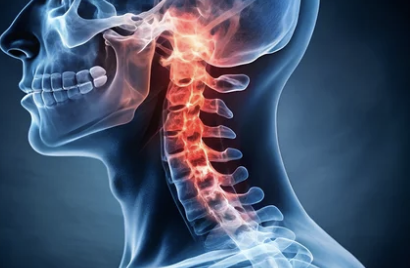

1. 목디스크란? 원인과 특징 이해하기

목디스크는 목뼈 사이에 위치한 디스크가 압박을 받아 탈출하거나 손상되어 발생하는 질환이에요. 디스크가 탈출하면서 신경을 누르게 되어 통증과 다양한 증상이 나타납니다.